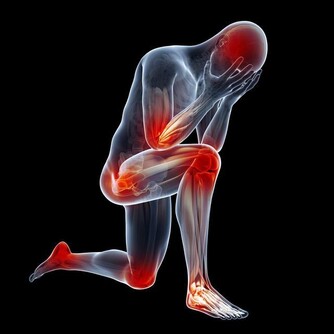

很多人沒有意識到長期吹空調造成的危害,覺得可能最嚴重的也就是得個感冒、頭暈頭疼而已,尤其是年輕人更不在意。

殊不知,冷空氣對關節的損害是很大的,如果不注意保暖,上了年紀很容易患上關節炎。

當人體遇冷時,血管收縮,血流速度減慢,血液中輸送的人體所需的各種養料和氧氣就會減少,而膝關節支撐人的身體,本身周圍血管少,血流速度就差,若穿著短褲、短裙則會使膝關節暴露在低溫環境,膝關節長時間受寒涼刺激,血液循環更慢,更易出現水腫和炎症改變,導致滑囊炎、滑膜炎等關節性疾病。